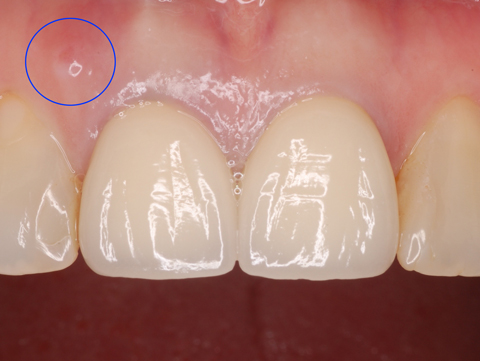

歯根破折

治療後6年経過。

歯肉の状態も良く審美的にも満足できる状態だったのですが、脱離して来院されました。

残念ですが歯根が破折していました。フィステルができています。

応急的に再装着しましたが、抜歯するしかありません。

セット時です。歯肉のレベルは上の写真と比べて殆ど変化していません。むしろ左右の対称性は6年後の方が増しています。

術前。すでに削ってしまってあった歯の再治療でした。歯の強度は削除量が大きいほど落ちてしまいます。神経を抜く場合でも最小限の削除にとどめることが、その歯の寿命を延ばすことになります。神経を抜くと歯が脆くなると良く言いますが(勿論神経が残っていた方が良いのです)その最大の要因は必要以上に切削するからです。